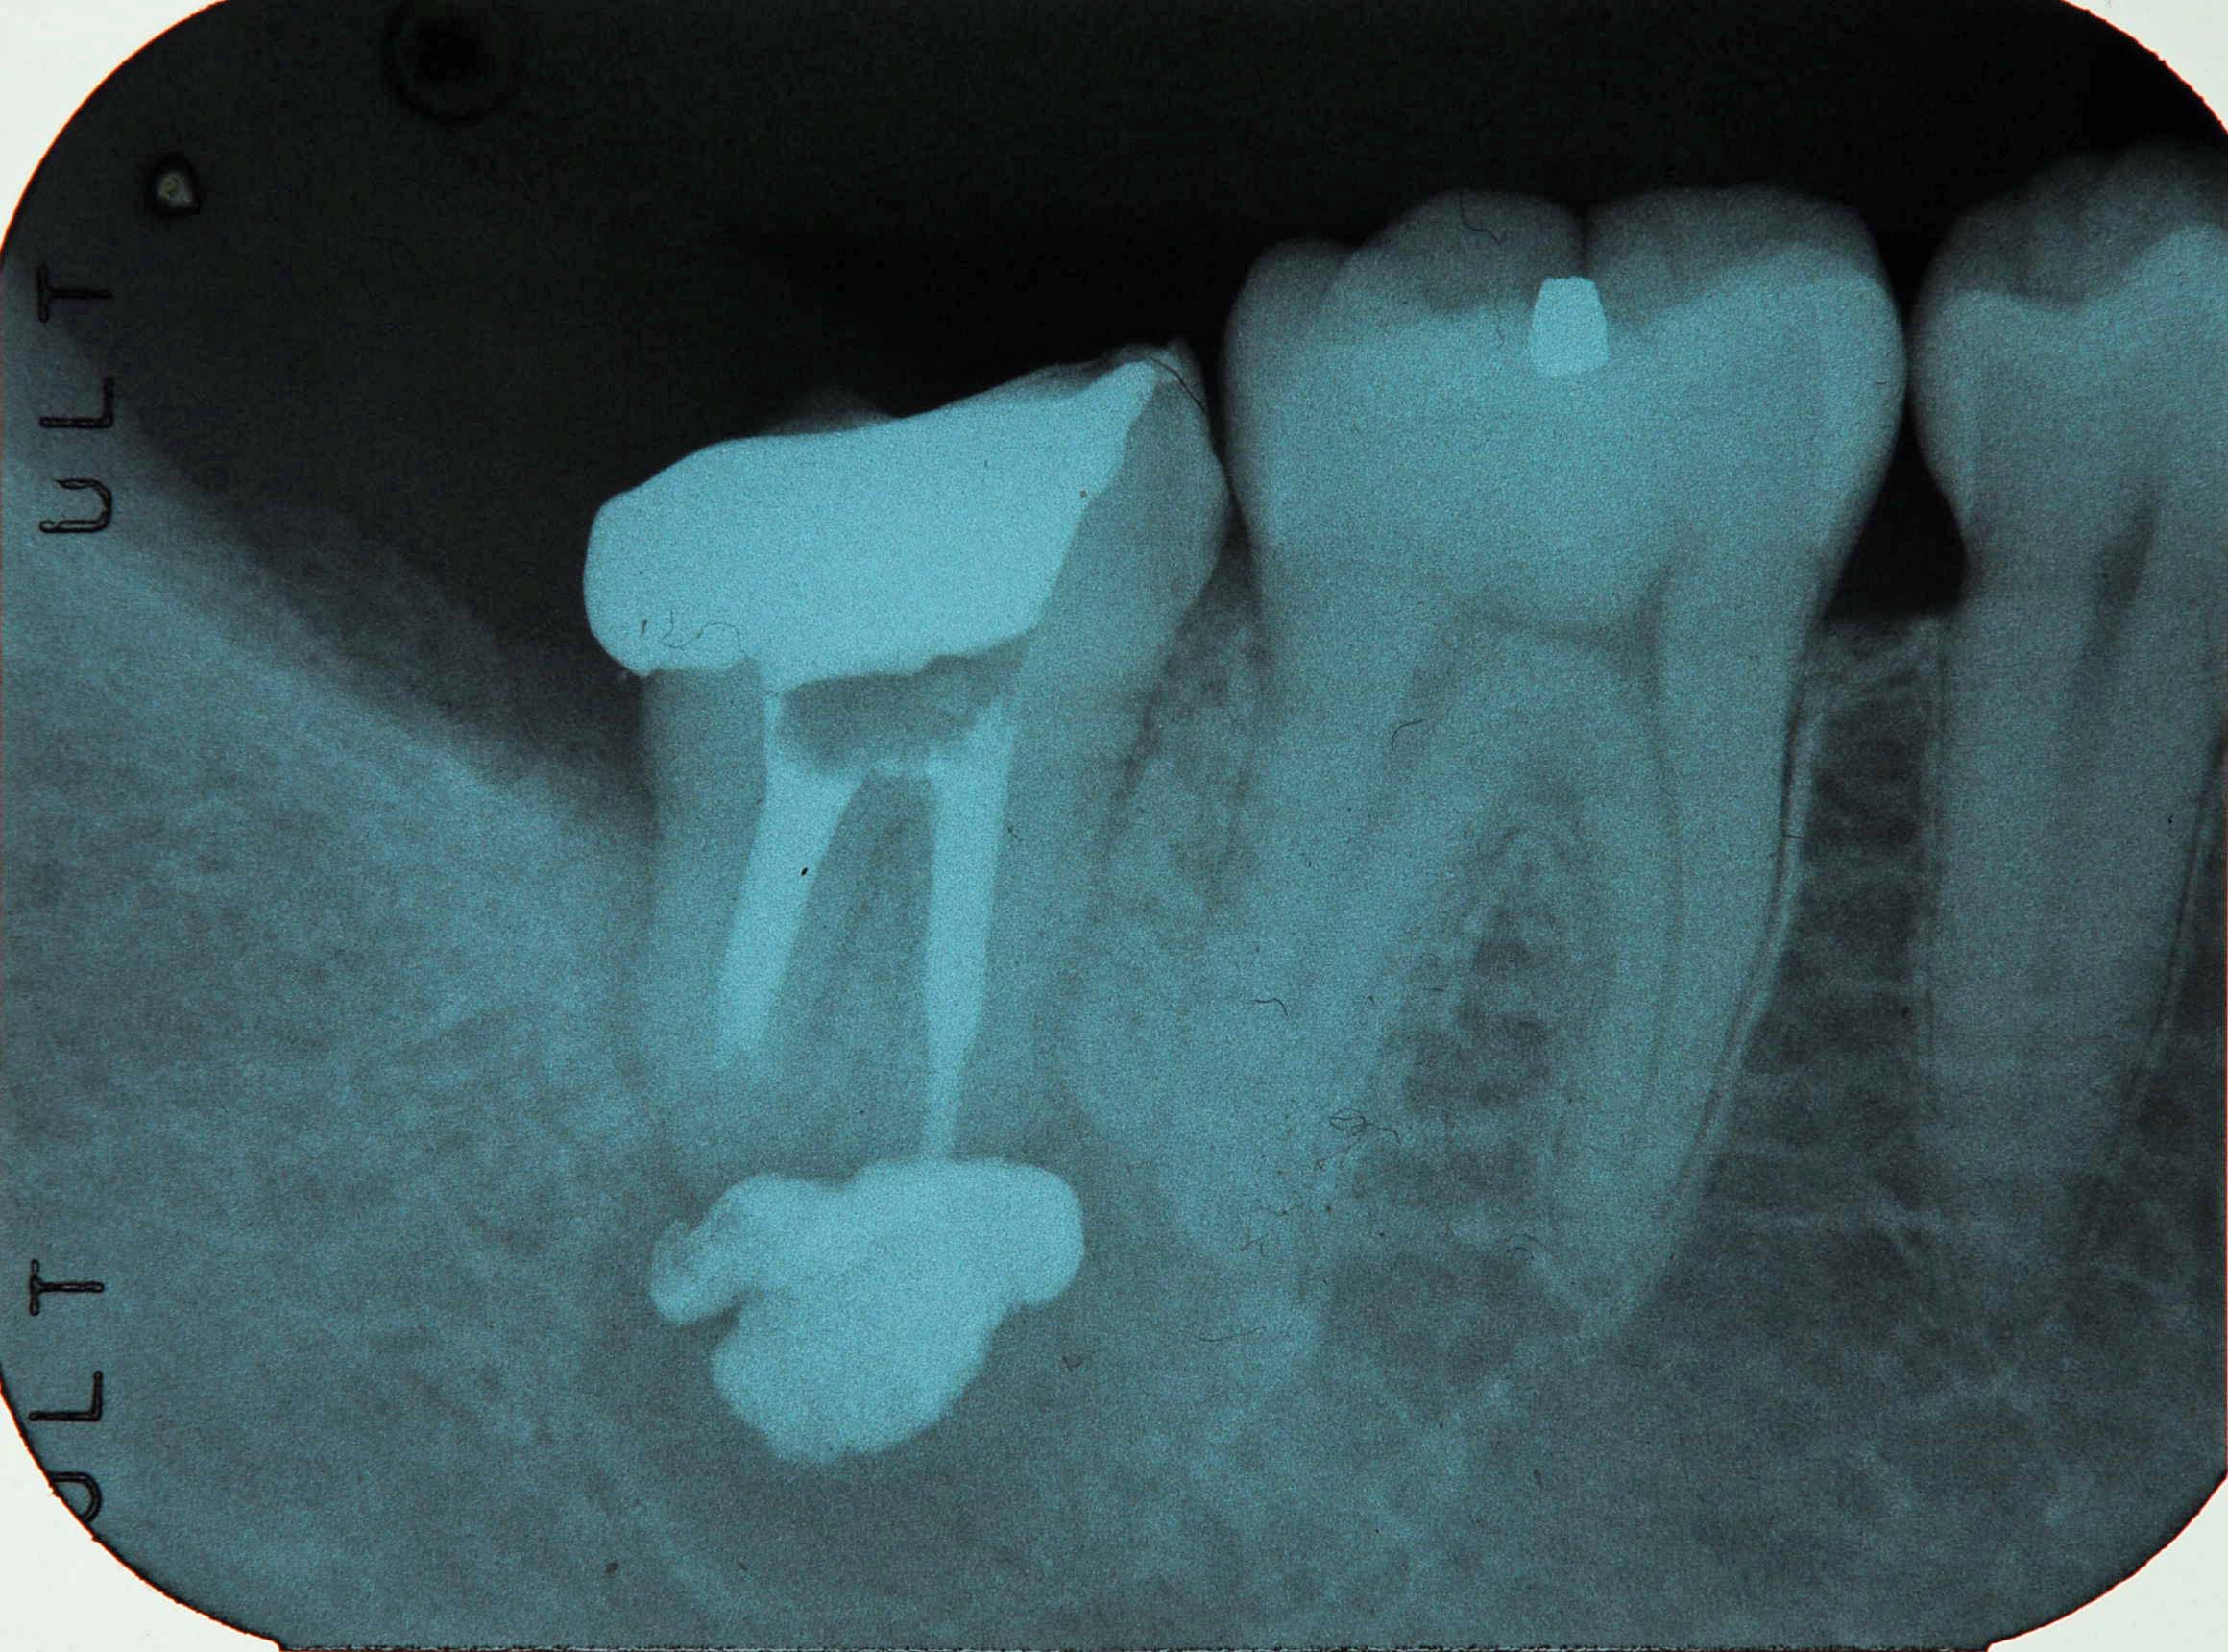

大きな根尖病変 2022 1/31 臨床アラカルト 2012年1月12日2022年1月31日 前々々回ブログ症例の別レントゲン。上段左写真(術前:根っこの先に大きな膿の袋があり骨が溶けている)、上段右写真(術中:病変に消毒薬を送り込む)、下段写真(根管治療後4カ月:病変が消失し、骨が再生しつつある)。再根管治療は比較的成功率の高くない治療と言われているが、昨年の研修の成果を発揮し、成功率を上げていきたい。(長谷川) 臨床アラカルト 根管治療 セミナー 基本治療 よかったらシェアしてね! URLをコピーしました! URLをコピーしました! ホワイトニング後の詰め物やり変え 英検1級初受験 関連記事 貼物作り 2025年11月27日 歯科は考古学? 2025年11月6日 奥歯の白い被せ物について 2025年6月2日 矯正とインプラントと補綴(被せ物)で審美と機能を回復中 2025年5月9日 圧下後の再生療法 2025年4月30日 卒後40年 2025年2月26日 骨造成 2025年2月25日 患者さんへのプレゼン準備 2025年2月20日